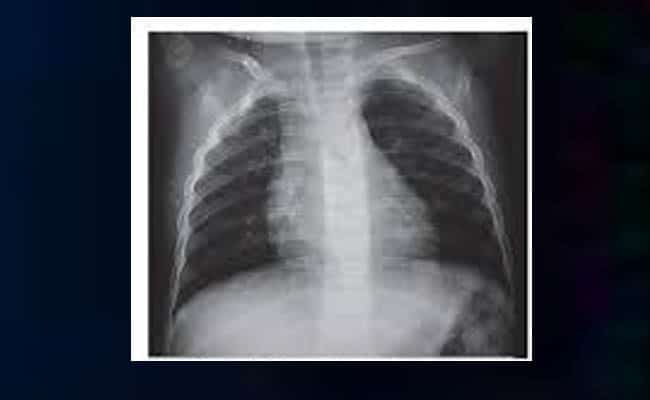

Neumatocele radiografía

En las radiografías, aparece con una cavidad de aire. Es decir, como un espacio en negro, vacío. En ocasiones, este quiste se ve perfectamente rodeado por los tejidos que impiden la salida del aire. Hay que agregar que con ayuda de la radiografía se puede ubicar perfectamente dónde se encuentra esta lesión. Además, se puede planificar la intervención quirúrgica necesaria en caso de que se decida removerlo.

Igualmente, con ayuda de la radiografía, se puede detectar la posible causa de la aparición del quiste. Cuando ocurre por infección, se notan problemas por la aparición de algún agente infeccioso en sus cercanías. No obstante, es mucho más evidente cuando este surge por una lesión. Esto se debe a que el traumatismo resulta apreciable a través del estudio radiográfico.

Hay que tener en cuenta que la radiografía puede arrojar la aparición de un quiste de este tipo, de manera casual. Es decir, se realiza el estudio radiográfico por otro motivo y aparece este peculiar quiste aéreo. Usualmente, los de aparición casual suelen no implicará mayores peligros y tienden a desaparecer espontáneamente.

No obstante, este tumor altera la función de respiración de la persona debe ser retirado quirúrgicamente. Antes de hacer la operación, lo mejor es valerse de una radiografía para ubicar donde se ubica este tumor y cómo debe ser abordado en el momento de la operación.